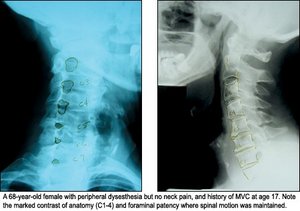

What we now understand is that in the process - due to the adverse anatomical effect of chronic biomechanical impairment - spinal segmental degenerative change involving discs, ligaments and bone occur at a much-advanced rate. I recently observed a 68-year-old female who had experienced a motor vehicle crash at age 17. She came in with complaint of right upper extremity numbness and tingling. Her history revealed she had not experienced any significant neck pain during her lifetime. X-ray examination revealed almost perfectly preserved anatomical structures in the upper cervical region (C1-4), while the lower cervical structures looked to be extremely aged. I also found well-established biomechanical impairments with rotary buckling in these same lower cervical motor units. The resulting loss of disc height, spondylosis and foraminal stenosis was so severe as to directly impinge nerve roots, and I could offer her only partial help. (See illustration below).